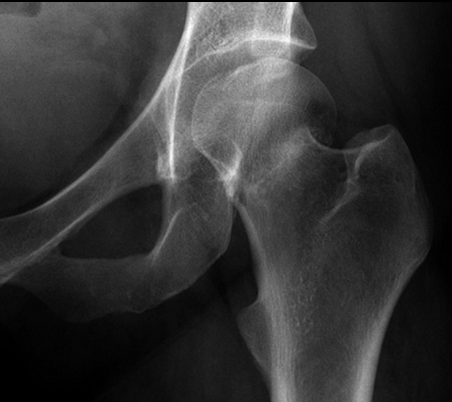

What is represented by 1 in the AP left hip radiograph?

1. femur

a. head

b. neck

c. greater trochanter

d. lesser trochanter

e. shaft

What is shown by 2, 3, 4 and 5 in this AP left hip radiofraph?

What is shown by the arrows on the lateral hip radiograph?

e. proximal shaft

2. acetabulum

3. ischial tuberosity

What condition is shown here?

neck of femur fracture

this is common in elderly people following a fall

Why does the neck of femur fracture appear different to most other fractures?

the fracture looks white rather than black

this is due to the impaction where the bones are driven into each other, leading to increased bone density at the site of the fracture

usually a fracture looks black as the bones are separated and air is present

Why is the lesser trochanter more visible in a neck of femur fracture?

the leg is pulled into external rotation when the neck of femur is fractured

this makes the lesser trochanter more visible anteriorly